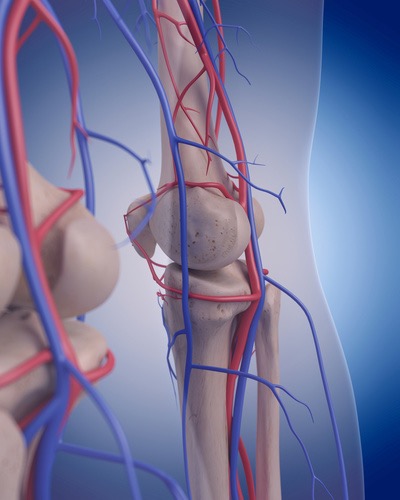

見逃している膝の痛みの原因靭帯

弓状膝窩靭帯リリーステクニック

この弓状膝窩靭帯を治療したことはありますか?この靭帯は腓骨頭の外側面から膝窩筋腱を横切って、関節包に付着しています。このように関節包に付着するということは当然関節包に刺激を加え、痛みを生じさせます。そして関節包自体もしくは隣接する膝窩筋に対しても滑走性の低下、筋高度を高めてしまいます。膝痛の最終調整には欠かせない靭帯調整リリーステクニックとなります。

Session18

注射やヒアルロン酸でも効かない膝の痛みを取る伏在神経リリーステクニック

ハンター管症候群(伏在神経麻痺)をご存知ですか?「ハンター管症候群」とは、聞きなれない疾患名ですが、まれに膝から下のふくらはぎの内側当りが痛む、しびれるという疾患があります。大腿神経の枝である伏在神経は内転筋と呼ばれる筋肉の傍を通り、ハンター管(内転筋管)と呼ばれる筋膜の管を通って、さらに下の方へと降りていきます。そして、膝の内側あたりで、膝蓋下枝と、内側下腿皮枝に分かれて、さらに下方へと伸びていきます。

膝~下腿の内側に広がる痛みやしびれは実はこの伏在神経由来の症状であることもあります。よく見逃されがちなところです。